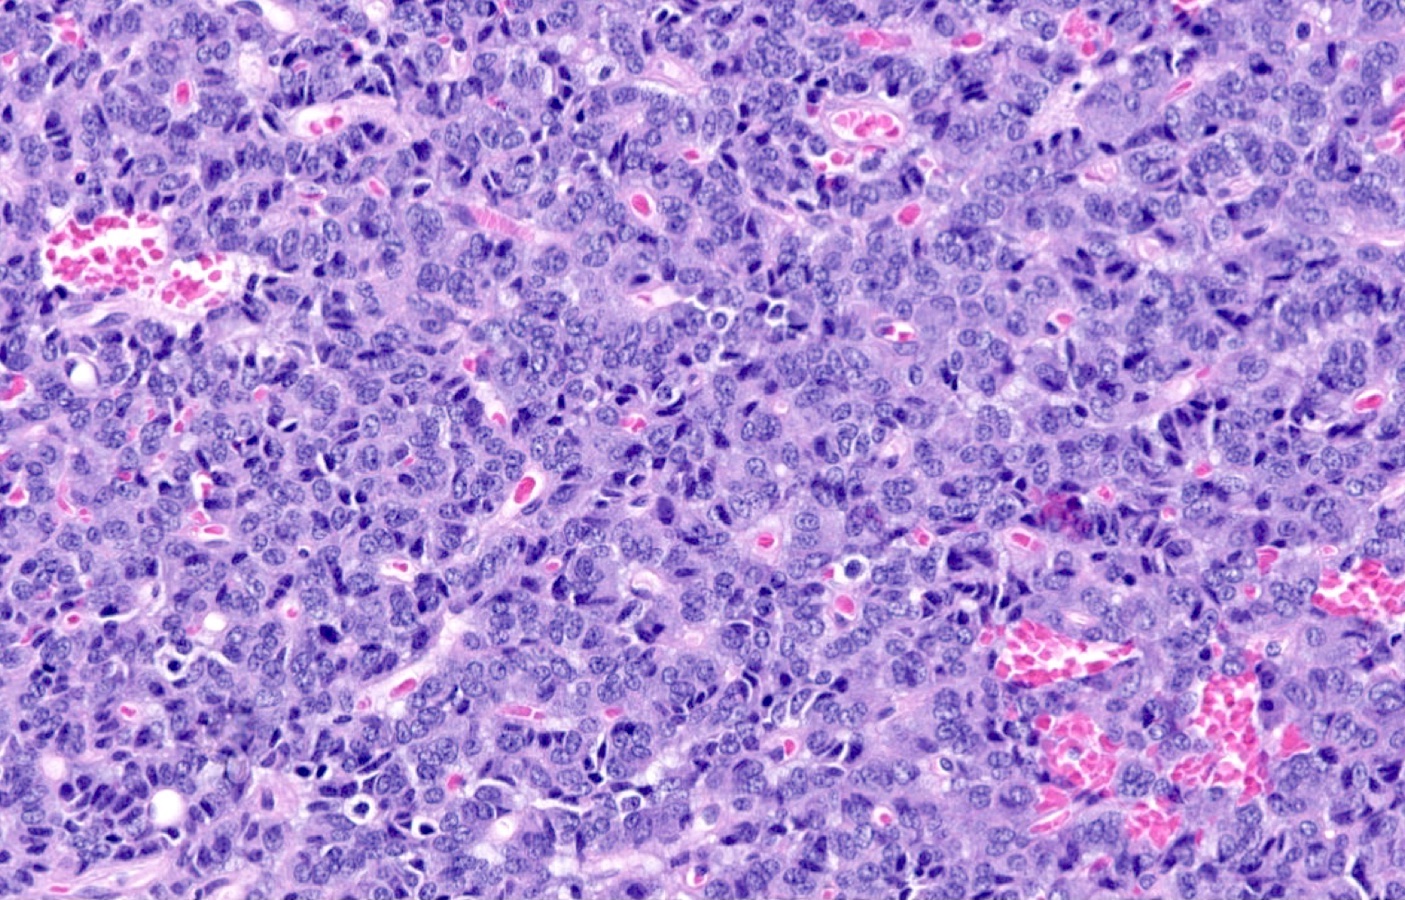

Microscopic (histologic) description

- Diagnostic criteria

- Neuroendocrine tumor with size ≥ 5 mm with < 2 mitoses/2 mm2 and absence of necrosis

- Neuroendocrine growth pattern (organoid, trabecular, rosette formation, nested) or pseudoglandular, follicular and papillary growth

- Tumor cells are uniform with a polygonal shape, round to oval nuclei with salt and pepper chromatin as well as inconspicuous nucleoli and moderate to abundant eosinophilic cytoplasm

- Spindle cells and clear cell features can be seen

- Stroma is fine and highly vascularized; hyalinization, cartilage or bone formation are possible

- Reference: Curr Oncol 2018;25:S86

Microscopic (histologic) images

Contributed by Philippe Joubert, M.D., Ph.D., Jijgee Munkhdelger, M.D., Ph.D. and Andrey Bychkov, M.D., Ph.D.